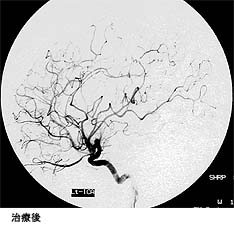

脳出血による半身麻痺と意識障害で発症した患者さまの治療前後の血管撮影を下に示します。(赤線内が脳動静脈奇形の部分)

手術中の血管奇形部分の写真。青丸部分に拡張した血管網が見られます。(下図)

(画像は、日本赤十字社医療センター 脳神経外科 野村竜太郎先生のご好意による)